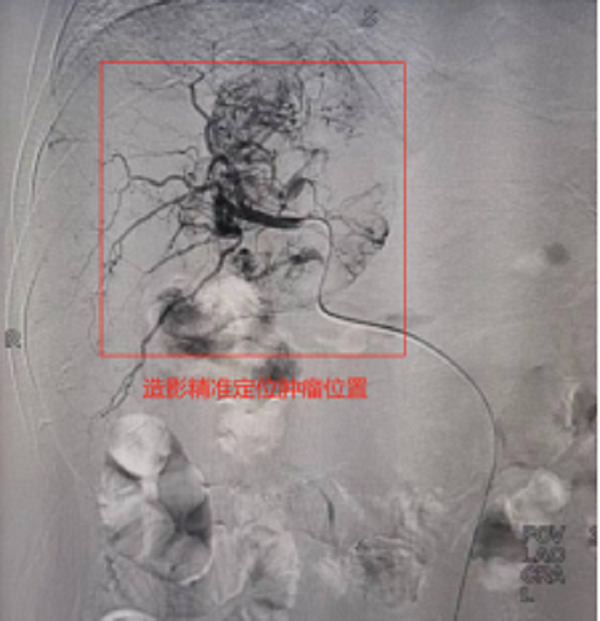

此次来院检查腹部增强CT提示:肝右叶占位性病变,考虑为原发性巨块肝癌,肿瘤大小达到60mmx84mm。患者之前已进行过结肠癌根治性右半结肠切除+胆囊切除术,病情复杂,身体虚弱,患者及家属强烈要求行微创介入治疗。经术前充分沟通及告知各种治疗方案的优缺点后,介入团队选择为患者行TACE介入微创治疗,后续将与靶向、免疫联合治疗达到肝癌的综合治疗。经过积极术前准备,普外科介入团队成功为患者实施了首例肝动脉化疗栓塞术,手术过程顺利,术后患者恢复良好,正在医院接受后续治疗。